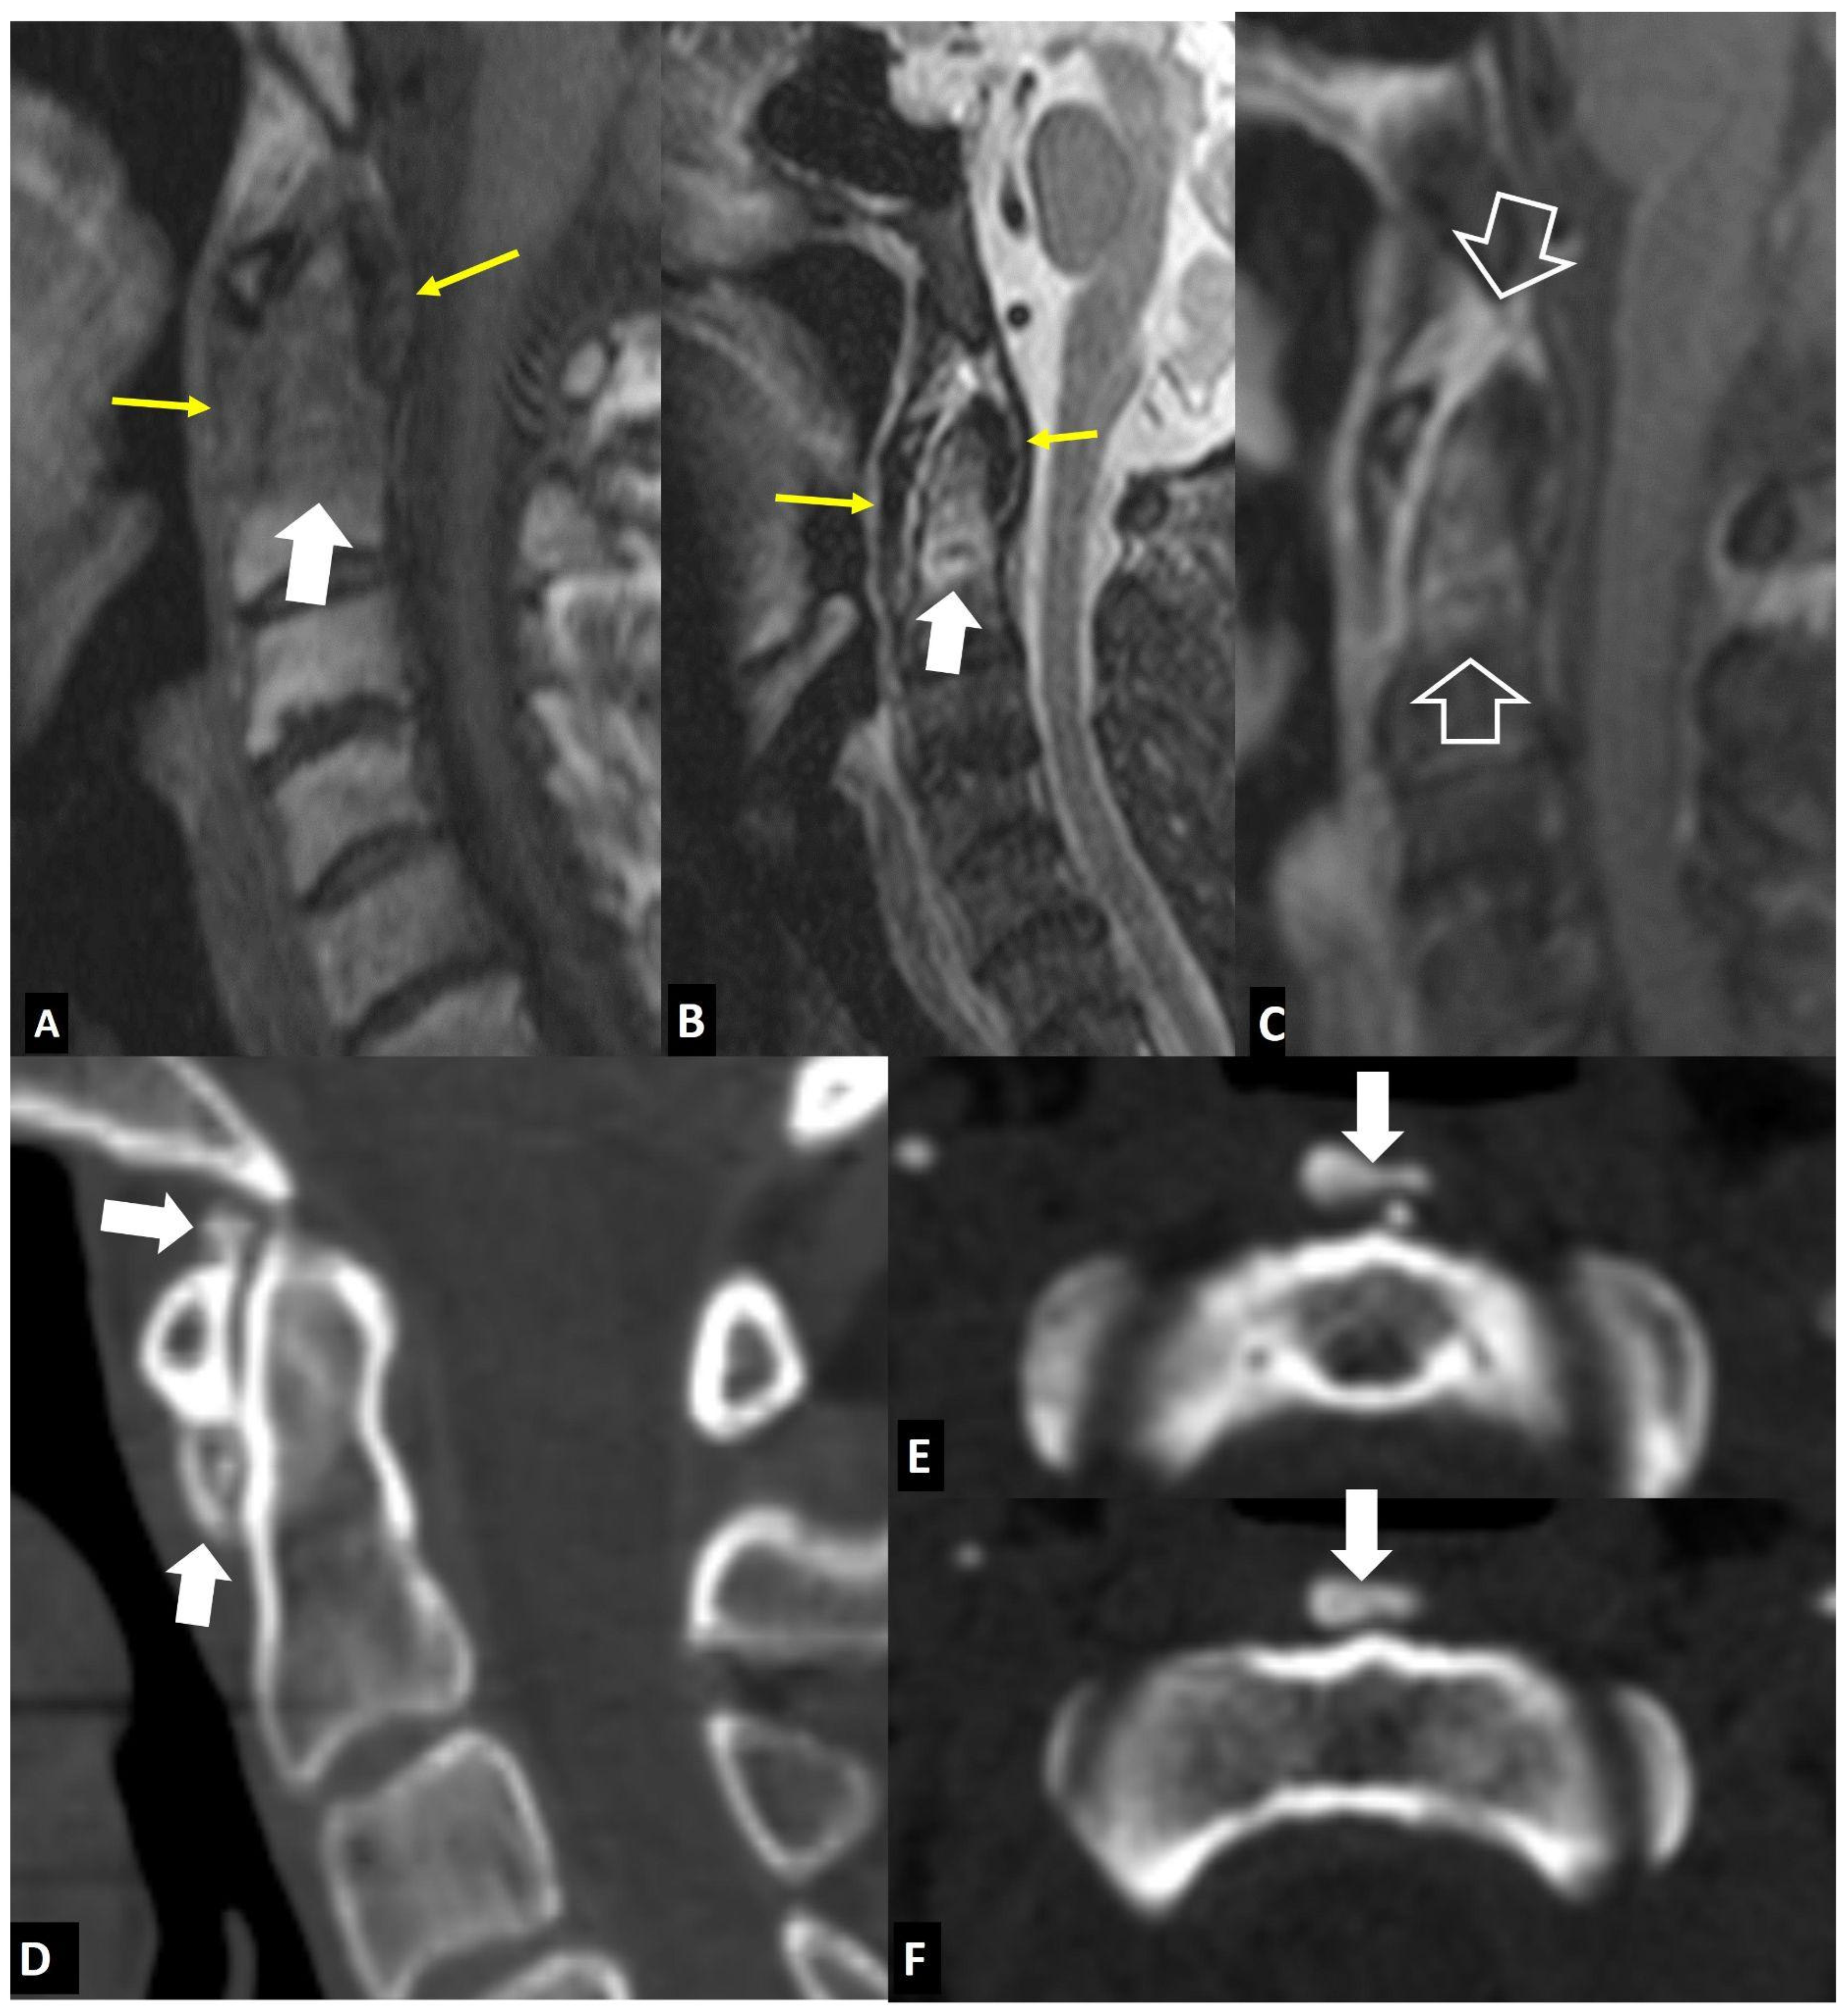

2.1.4. Destructive Spondyloarthropathy

- Andersson, O. Rontgenbilden vid spondylarthritis ankylopoetica. Nord. Med. Tidskr. 1937, 14, 2000–2002. [Google Scholar]

- Hunter, T. The spinal complications of ankylosing spondylitis. Semin. Arthritis Rheum. 1989, 19, 172–182. [Google Scholar] [CrossRef] [PubMed]

- Kim, S.-K.; Shin, K.; Song, Y.; Lee, S.; Kim, T.-H. Andersson lesions of whole spine magnetic resonance imaging compared with plain radiography in ankylosing spondylitis. Rheumatol. Int. 2016, 36, 1663–1670. [Google Scholar] [CrossRef] [PubMed]

- Bennett, A.N.; Rehman, A.; Hensor, E.M.A.; Marzo-Ortega, H.; Emery, P.; McGonagle, D. Evaluation of the diagnostic utility of spinal magnetic resonance imaging in axial spondylarthritis. Arthritis Rheum. 2009, 60, 1331–1341. [Google Scholar] [CrossRef] [PubMed]

- Kabasakal, Y.; Garrett, S.L.; Calin, A. The epidemiology of spondylodiscitis in ankylosing spondylitis—A controlled study. Br. J. Rheumatol. 1996, 35, 660–663. [Google Scholar] [CrossRef]

- Madsen, K.B.; Jurik, A.G. MRI grading method for active and chronic spinal changes in spondyloarthritis. Clin. Radiol. 2010, 65, 6–14. [Google Scholar] [CrossRef]

- Park, Y.-S.; Kim, J.-H.; Ryu, J.-A.; Kim, T.-H. The Andersson lesion in ankylosing spondylitis: Distinguishing between the inflammatory and traumatic subtypes. J. Bone Jt. Surg. Br. 2011, 93, 961–966. [Google Scholar] [CrossRef]